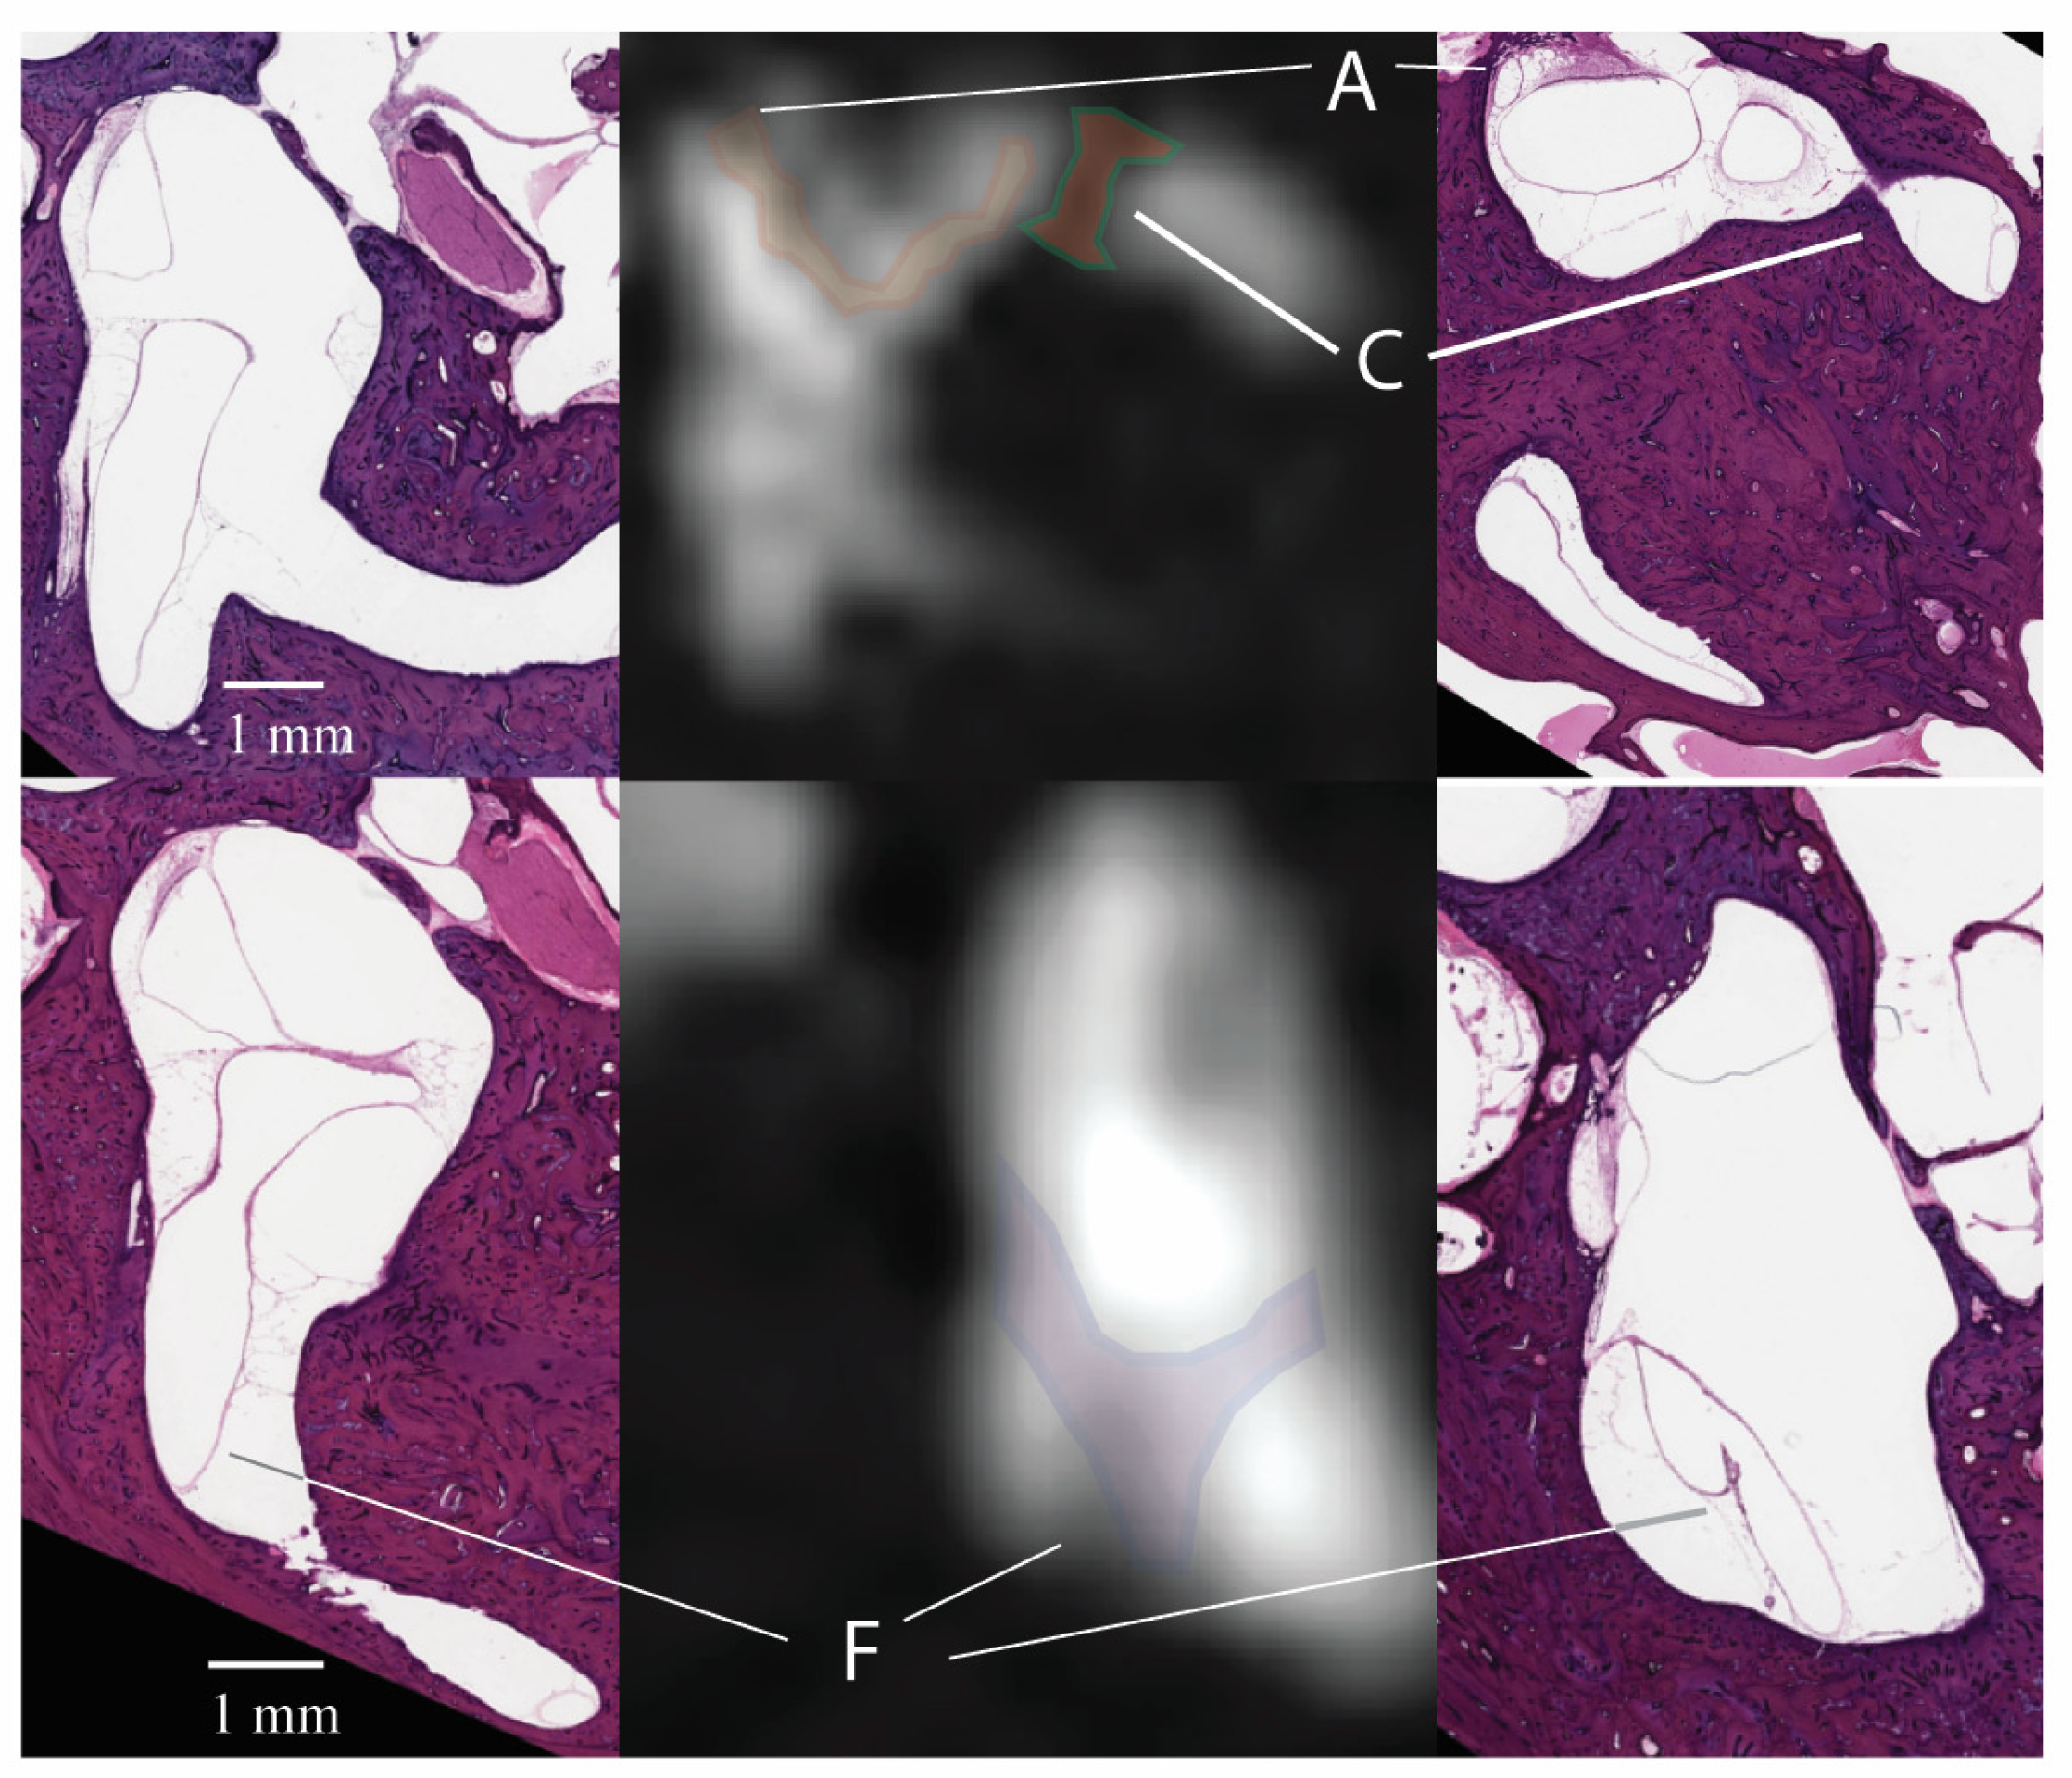

3.1. Signal Areas in the Inner Ear

3.2. Signal Areas in the Eye